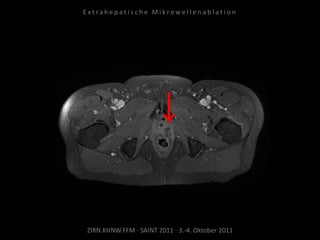

Bildgebung vor MWA:

MRT 03.02.2010

Situation:

Bei Z.n. Prostataresektion + Radiatio

+ Seed nun Rezidiv in kritischer

Position.

Ziel:

Tumordestruktion unter Schonung

der Nachbarstrukturen.

Ablation am 25.03.2010:

1 Nadelposition, 45 W, 7 Min.

Während der Ablation werden

Harnleiter, Harnblase und Rektum

zwecks Hitzeableitung gespült zur

Vermeidung thermischer Schäden.